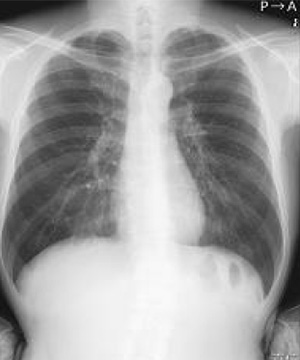

エックス線を利用して検査をするいわゆる“レントゲン撮影”です。

胸部、腹部、全身の骨の撮影を行います。心臓の大きさや肺の異常陰影、ガスの状態や骨の形、骨折の有無、関節の状態などがわかります。

当院ではフラットパネル(FPD)というシステムを導入し従来よりもエックス線の感度が高く低被ばくで撮影ができるようになりました。撮影効率も向上し撮影待ち時間も短縮しています。